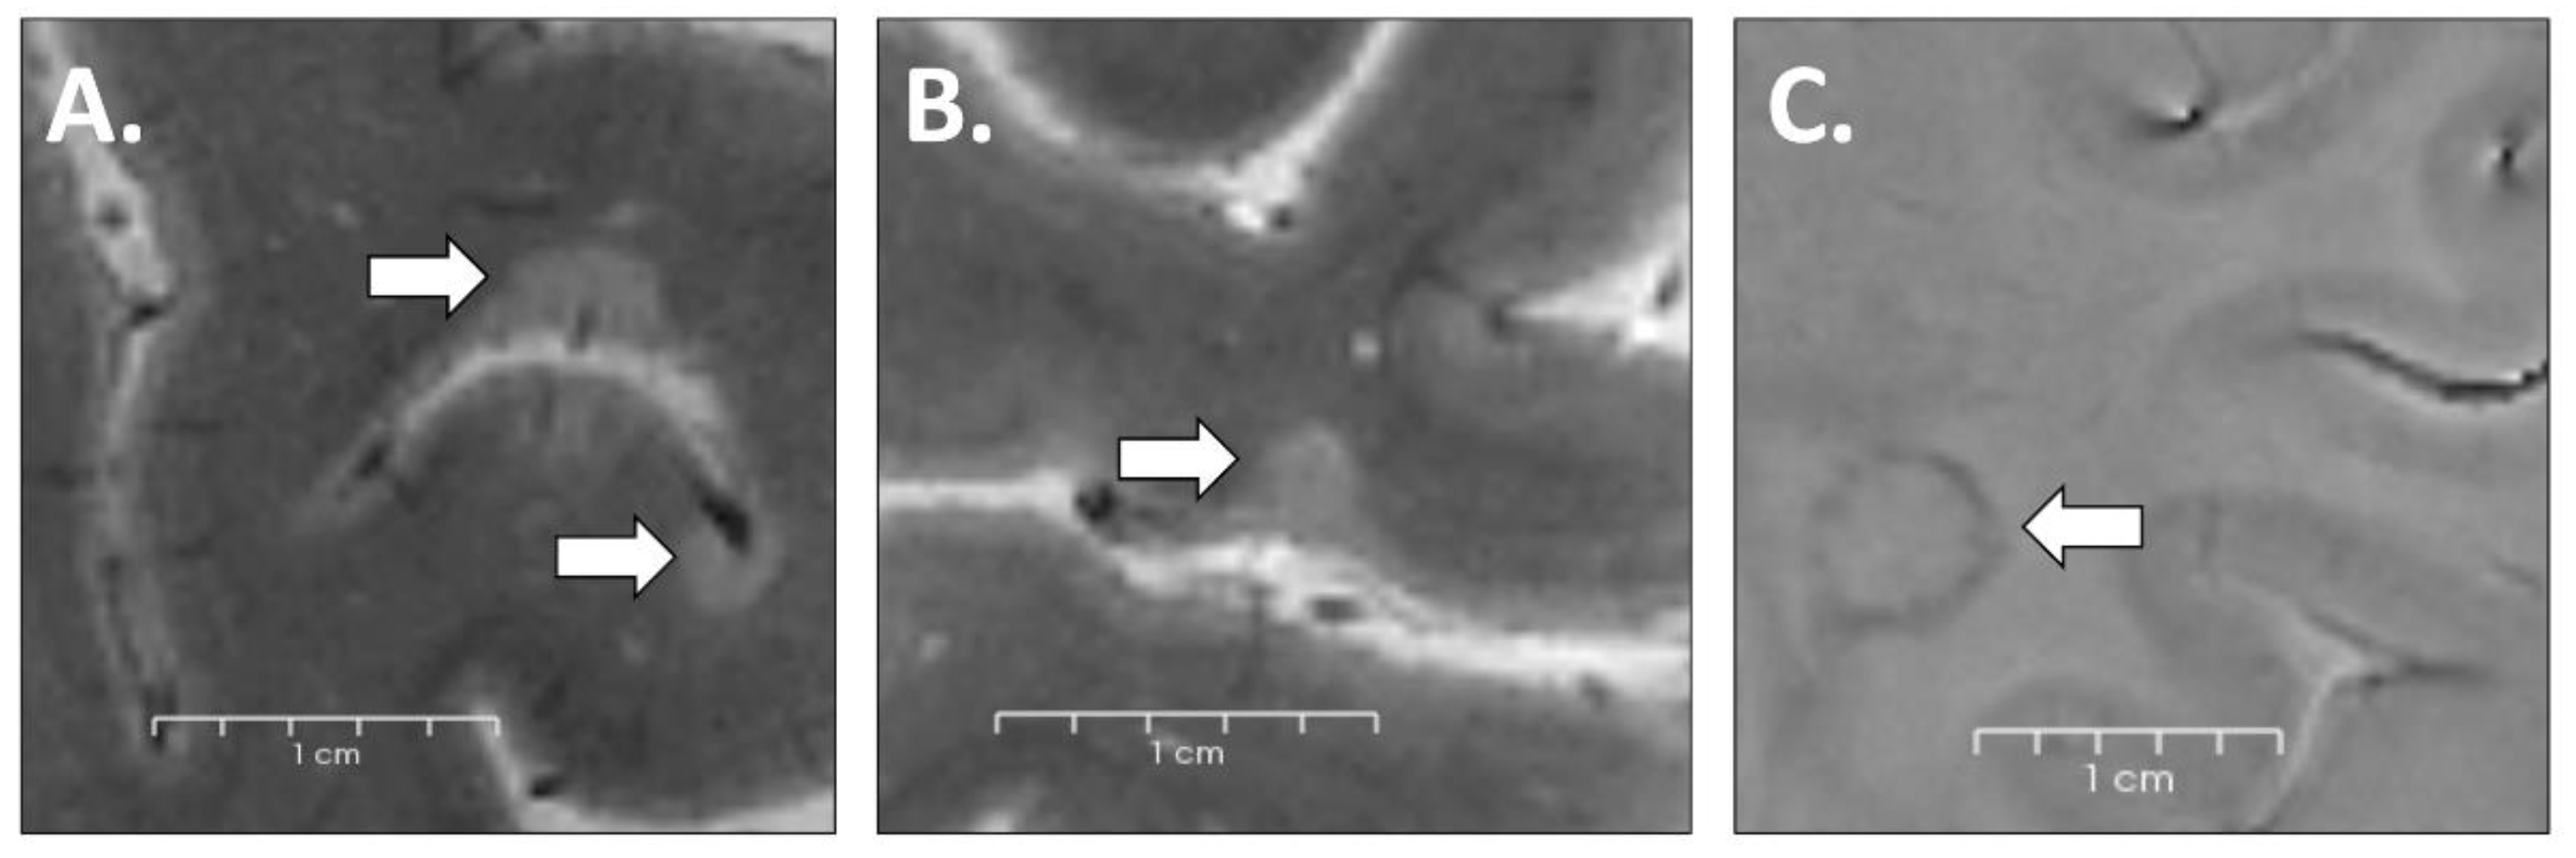

2.4. Lesion Identification